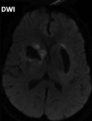

What is diffusion-weighted imaging, and why is it used in stroke?

DWI: Type of MRI sequence that measures diffusion of water molecules within tissues Highly sensitive to ischaemic changes

34

What does an ischaemic stroke look like on DWI brain?

Hyperdense lesion